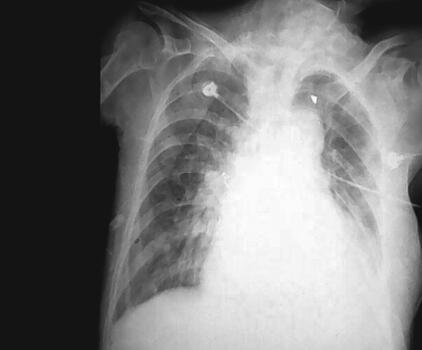

入院后立即气管插管,呼吸机辅助通气,心电、血压、氧饱和度监测,积极控制感染:头孢唑肟2.0g,每12小时1次;解痉、化痰,改善通气,改善心功能,强心、利尿、硝酸酯类扩血管治疗。经呼吸机治疗,很快意识好转,但是心功能没有明显恢复,心肌标志物检查一直在升高,TnI最高在33.8μg/L,BNP最高在17807pg/ml,呼吸机撤机困难,在呼吸机给予SIMV方式后出现急性左心衰竭,心源性休克,血压降至71/39mmHg,立即给予血管活性药物调整血压。4月10日患者体温开始升高,双肺痰鸣音增加,痰量增加,并为黄痰,胸部X线片见图2,痰涂片为革兰阳性球菌,革兰阴性球菌和革兰阳性杆菌,痰培养多次为鲍曼不动杆菌,属多重耐药型。经调整抗生素后体温逐渐好转,痰量减少,同时血中WBC在10×109/L左右,而且逐渐下降,中性粒细胞75%左右,逐渐准备撤机,胸部X线片见图3。但是患者在撤机过程中多次发作心力衰竭,出现咳粉红色泡沫样痰,同时血BNP指标逐渐上升,最高达45445.4pg/ml。4月17日将呼吸机调为机控A/C方式后逐渐好转。于4月29日行气管切开术。此时痰培养汇报均为鲍曼不动杆菌和铜绿假单胞菌,体温在38℃左右,双肺仍有大量痰鸣音、湿啰音,胸部X线片见图4,心率102次/分,血BNP 11969.6pg/ml,WBC 9.23×109/L,N 77.41%,根据药敏结果更换抗生素为头孢哌酮-舒巴坦钠3.0g,每8小时1次,联合口服米诺环素100mg,每天2次治疗,患者体温逐渐恢复,心率下降至60次/分左右,症状逐渐缓解(胸部X线片见图5)。血BNP降至6995pg/ml。但是呼吸机一直不能撤离。在抗感染的同时一直给予扩血管、利尿、改善心肌血供、改善心功能治疗,给予米力农、心钠素治疗,心力衰竭症状明显缓解,但是撤机仍然困难。终因高龄,全身状态差,出现尿路感染。尿培养、痰培养多次出现念珠菌生长(光滑念珠菌为主),尿中出现屎肠球菌生长2次。肾功能逐渐下降,血Cr最高至114μmol/L。并出现高热,白细胞升高,贫血(胸部X线片见图6)。将抗生素改为美罗培南加利奈唑胺及伏立康唑,症状逐渐改善,肾功能恢复正常,血常规正常,体温恢复正常。

图4 炎症明显增多,肺淤血也加重